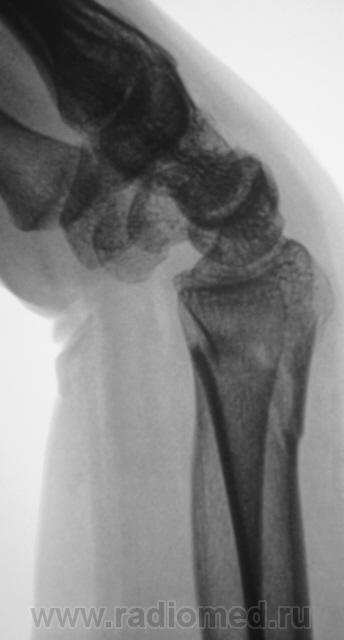

Травма.   Пациент направлен на рентгенографию лучезапястного сустава.

Вывих трапеции и гороховидной костей, ну и перелом "луча" в т.м., куда же без него.